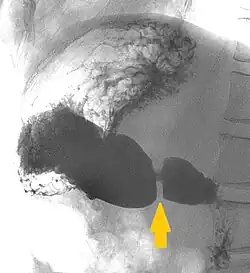

Eine Verengung mit funktionellem Verschluss wird als Pylorusstenose oder Magenausgangsstenose bezeichnet. Die hypertrophe Pylorusstenose ist vorwiegend nerval bedingt und tritt nahezu ausschließlich bei Kindern auf. Die dabei auftretende Hypertrophie der Ringmuskulatur des Magenausgangs muss chirurgisch beseitigt werden.[8] Über erste Entfernungen des Pylorus bei drei Hunden berichtete im Jahr 1810 der Mediziner und spätere Militärarzt Daniel Carl Theodor Merrem.[9] Die erste Pylorusresektion am Menschen führte Jules Péan am 9. April 1879 durch.[10] Gelegentlich kann eine Pylorusstenose auch durch Verengung des Pyloruskanals infolge von Magenkrebs oder Vernarbungen nach Magengeschwüren entstehen.[11] In der Tiermedizin treten Pylorusstenosen vor allem bei Hunden auf. Angeborene Pylorusstenosen sind vor allem beim Deutschen Boxer und beim Boston Terrier häufig, erworbene treten vor allem bei Zwerg- und brachycephalen Rassen auf.[12]